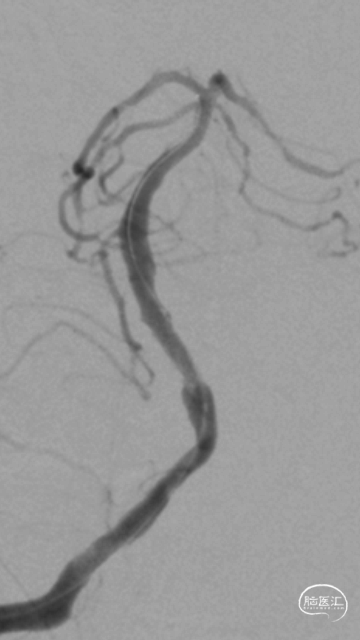

右侧桡动脉穿刺造影:右侧椎动脉优势;左侧椎动脉发自弓上,纤细迂曲;双侧后交通动脉欠发达。

超选右侧椎动脉造影:右侧椎-基底动脉连接处次全闭塞,前向血流 mTICI 2b级。